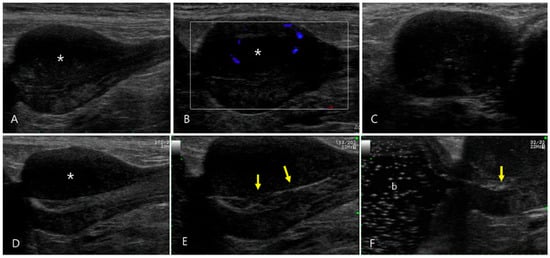

2.4. Case 4